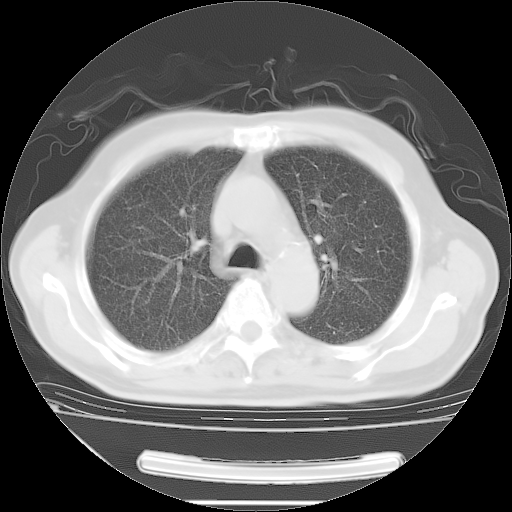

今天复查肺部CT,发现双肺广泛磨玻璃样改变。所以我把3月19日和5月9日相隔50天的肺部CT上传。请大家会诊。

2009年3月19日肺部CT片。

2009年3月19日肺部CT

5月9日肺部CT(在4月27日齐鲁医院肺部CT描述部分肺组织磨玻璃样改变,12天后肺组织广泛磨玻璃样改变)

大致读了系列胸部CT:纵隔窗无明显异常,肺窗:从4、27至今:主要是双肺中下野外带可见毛玻璃样改变,目前处于急性肺泡炎阶段,至于原因考虑1、结替组织或胶原血管性疾病所致?2、恶性疾病如恶组在肺部所致的表现或细支气管肺泡癌?3、药物或其它原因如肺蛋白沉着症所致肺泡炎目前不太可能?总之,明天就去请我院的呼吸科、感染科、血液科和临免专家会诊哈。